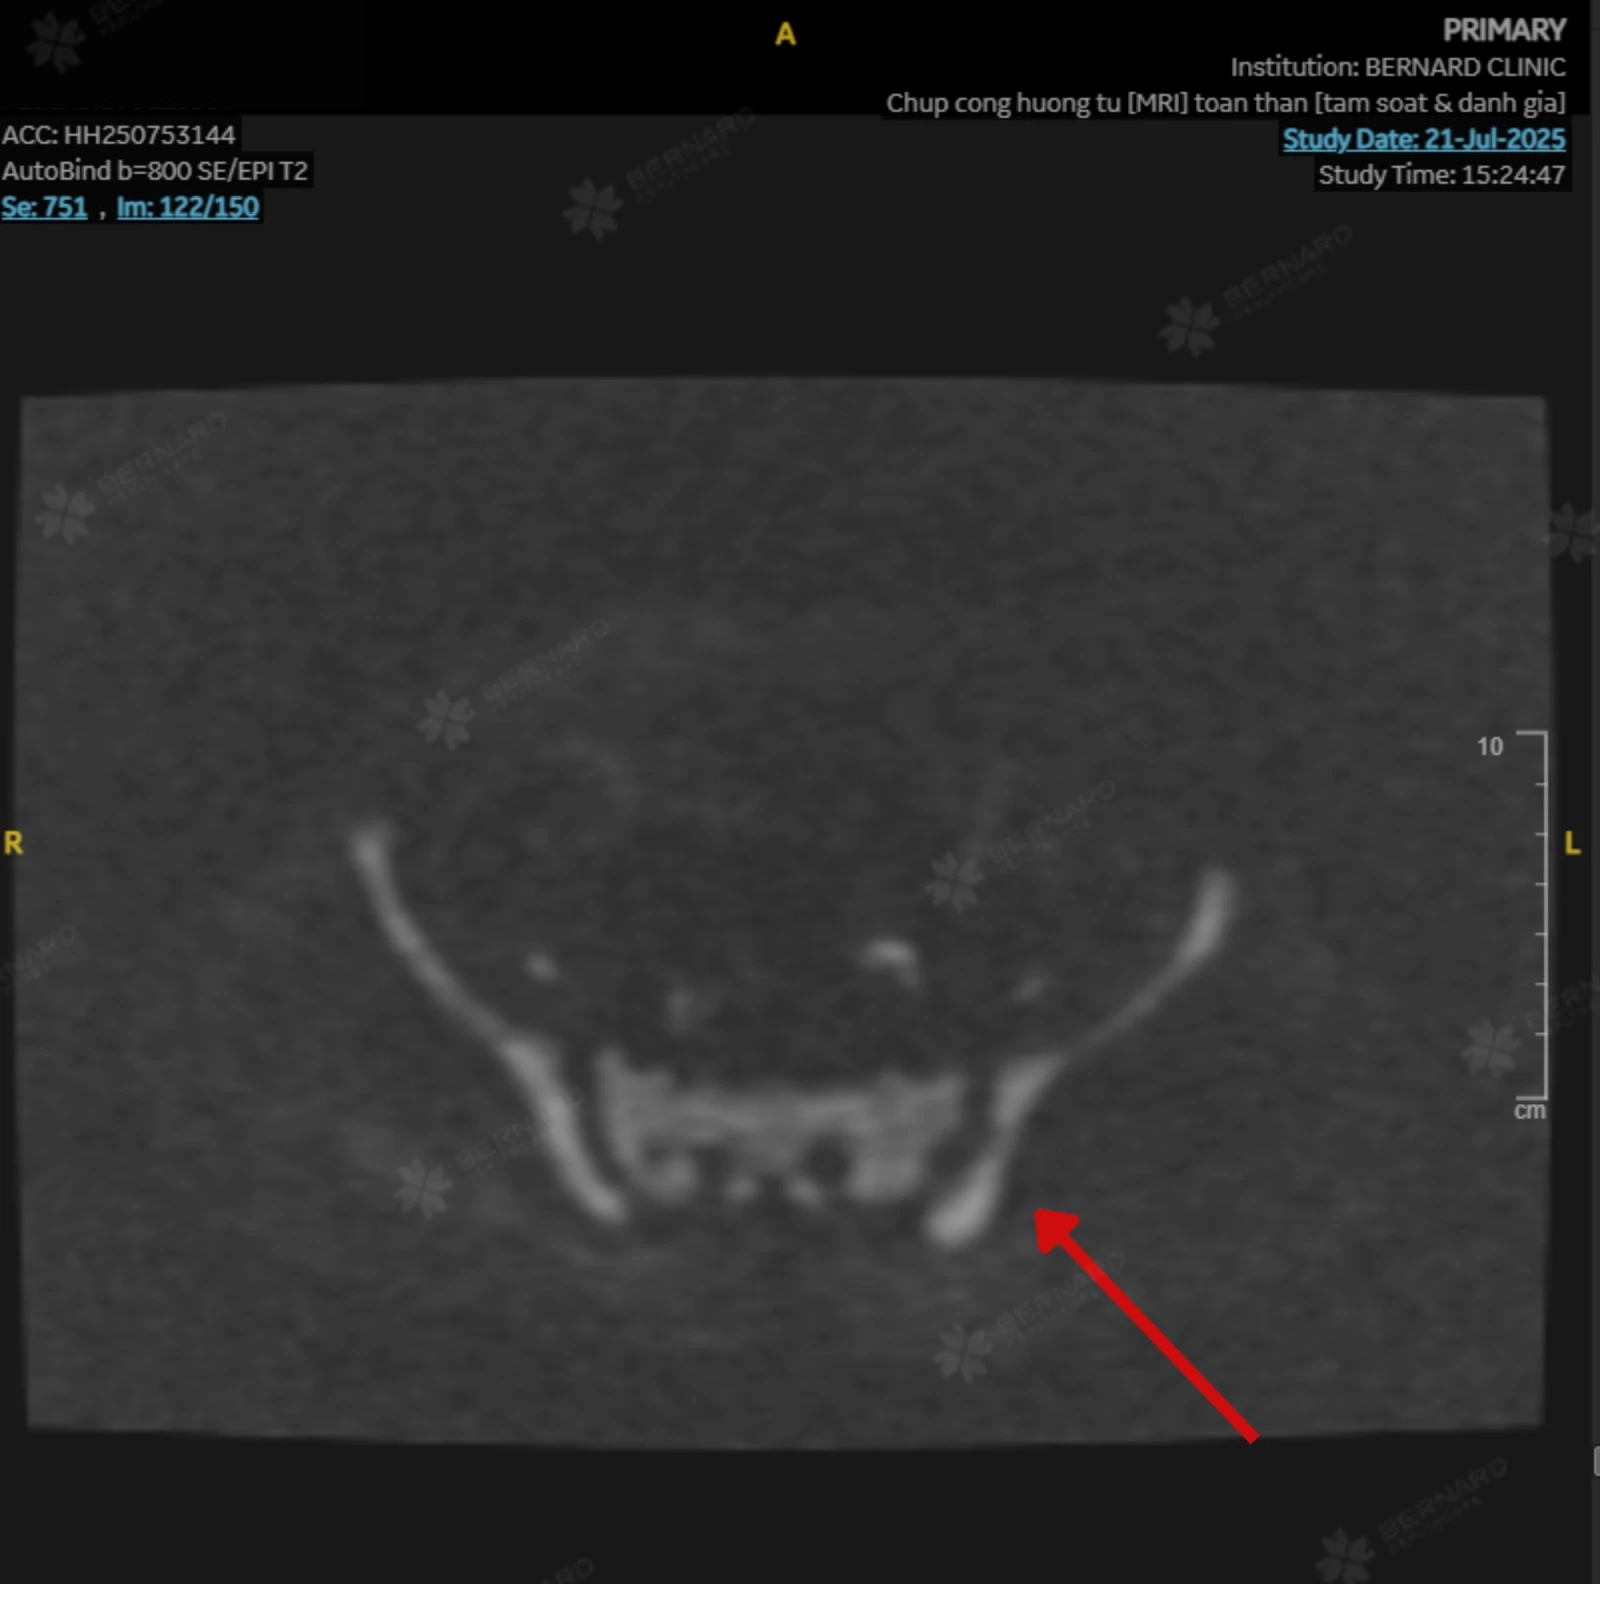

Kết quả MRI toàn thân ghi nhận những thay đổi bất thường ở vùng cột sống, xương sườn, xương chậu và đầu trên xương đùi hai bên, cùng tín hiệu bất thường ở vùng lách. Các dấu hiệu này gợi ý tình trạng tăng sản tủy xương (bone marrow hyperplasia).

Hình ảnh chụp MRI toàn thân của chị P. được trích xuất từ hệ thống PACS tại Bernard